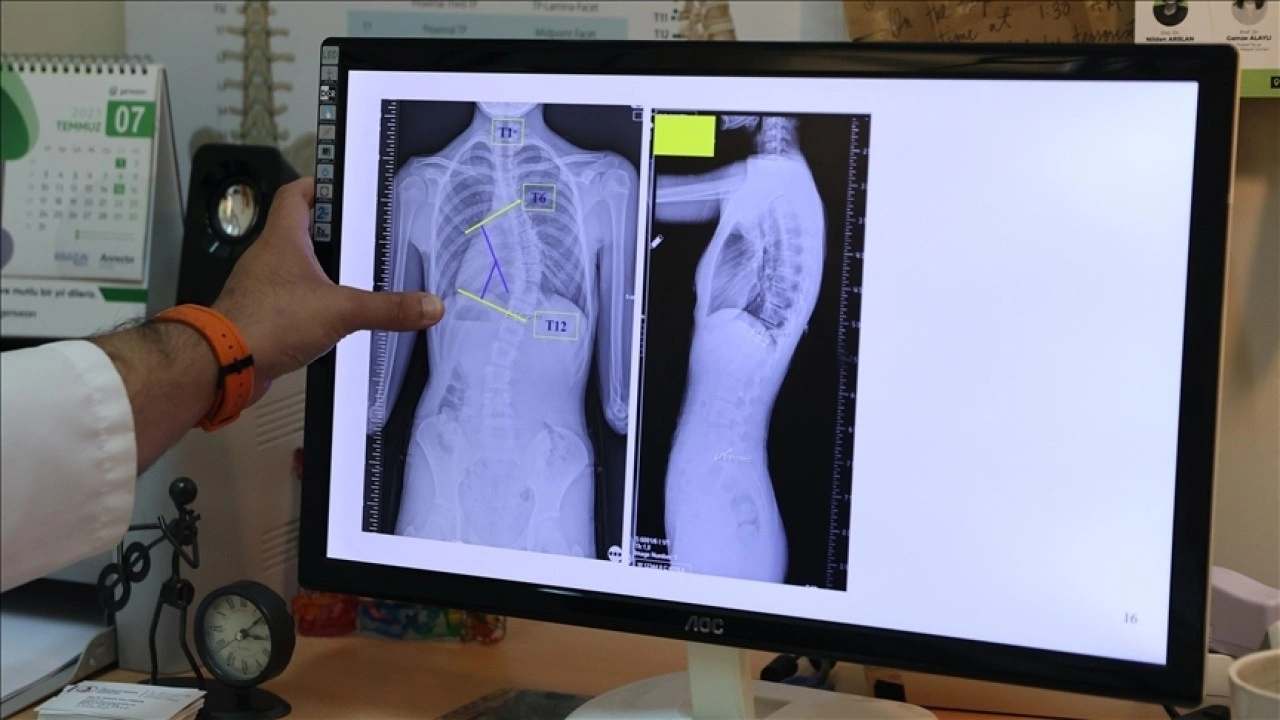

OMÜ'den yapılan yazılı açıklamaya göre Coşkun, skolyozun omurganın yana doğru eğilmesiyle karakterize edilen ve zamanla 3 boyutlu bir deformiteye dönüşebilen bir hastalık olduğunu vurguladı.

Skolyozun ilk başta yana doğru bir eğrilik gösterdiğini ancak zamanla omurganın kendi içinde burkulma hareketi yaparak ciddi bir deformiteye yol açabildiğini aktaran Coşkun, Türkiye'de değişen bölgelerde yüzde 0,5 ila yüzde 6 oranında skolyoz vakası olduğunu bildirdi.

Skolyozun erken teşhisi ile tedavi şansının yükseldiğini belirten Doç. Dr. Coşkun, "10 derecenin altındaki eğrilikler postür bozukluğu olarak adlandırılır ve bu durum modern çağın hastalığıdır. Özellikle tablet ve telefon kullanımının artması, spor aktivitelerinin azalması duruş bozukluğunun başlıca nedenleri arasındadır. Diğer yandan nörolojik rahatsızlıklar da skolyozu tetikleyebilir. Ayrıca aile geçmişinde skolyoz vakası olan bireylerde hastalığın görülme olasılığı yüzde 30 daha yüksektir." bilgisini paylaştı.